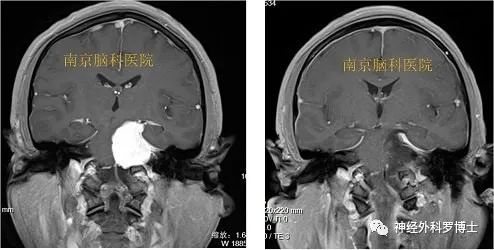

(见下图,上三张为术前,下三张为同一层面术后复查对比,提示肿瘤全切除)

患者48岁女性,以“右侧面部疼痛”为主诉入院。

门诊诊断为三叉神经痛。进了病房后,给予做磁共振检查显示为岩斜区肿瘤。

术前磁共振MRI增强显示中颅窝岩骨尖部和后颅窝(小脑幕下、斜坡)病变,术后1天磁共振复查显示肿瘤全切,无残留,术后患者恢复良好,没有不良症状发生。通过颞下经小脑幕入路一次手术全切病变,避免分期二次手术的痛苦。